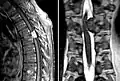

Meningeom im Spinalkanal Kernspintomographie. Links T1 sagittal mit Kontrastmittel, rechts T2 coronar